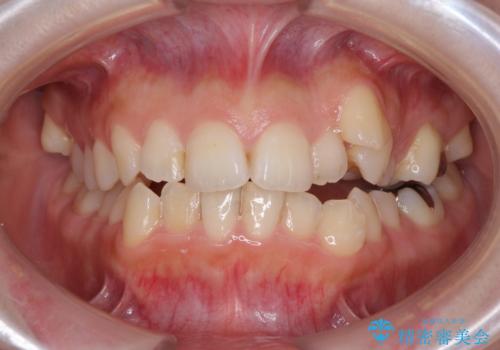

上下前歯が接触しない オープンバイトをインビザラインで改善

オープンバイト(開咬)を非抜歯インビザラインで治す

顕著な八重歯をインビザラインで治せるところまで改善